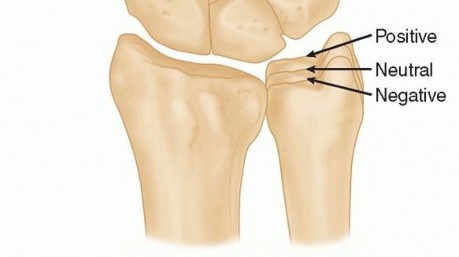

Let us turn our attention to the distal forearm and the critical relationship between the lengths of the radius and ulna, known as ulnar variance. In a normal wrist with neutral ulnar variance, the distal articular surfaces of the radius and ulna are flush. Under these conditions, the radius bears approximately 80% of the axial load transmitted across the radiocarpal joint, while the ulna, via the triangular fibrocartilage complex (TFCC), absorbs the remaining 20%.

However, when a patient exhibits negative ulnar variance—where the ulna is anatomically shorter than the radius—this delicate load-sharing ratio is severely disrupted. Biomechanical studies have shown that even a 1 to 2 mm negative variance can shift the load distribution such that the radius bears up to 95% of the transcarpal forces. This disproportionately high load is concentrated directly across the radiolunate joint. The lunate is subjected to immense shear and compressive forces, particularly at its radial aspect, where its articulation with the rigid lunate fossa of the distal radius is far less compliant than its articulation with the thicker, shock-absorbing TFCC on the ulnar side.

The radial shortening osteotomy directly and elegantly addresses this biomechanical imbalance. By surgically shortening the radius by a meticulously calculated 2 to 3 millimeters, we effectively "level" the joint. This intervention decreases joint compression forces at the radiolunate joint and redistributes them ulnarward to the ulnolunate joint and the TFCC. Furthermore, shortening the radius relatively lengthens the extensor and flexor musculotendinous units crossing the wrist joint. This "de-tensioning" effect further diminishes the overall static compressive forces acting on the carpus, providing a significant biological advantage over ulnar lengthening procedures, which do not offer this musculotendinous relaxation.

Meticulous radiographic evaluation is the foundation of our preoperative plan. We require high-quality, standardized posteroanterior (PA) and lateral radiographs of the affected wrist. The PA view must be taken with the patient's shoulder abducted to 90 degrees, the elbow flexed to 90 degrees, and the forearm in neutral rotation. This specific positioning is critical, as forearm pronation or supination artificially alters the apparent ulnar variance on the radiograph.

Once standardized images are obtained, we meticulously measure the ulnar variance. We draw a line transverse to the long axis of the radius at the level of the sclerotic subchondral bone of the lunate fossa, and a second parallel line at the distal articular surface of the ulnar head. The distance between these lines dictates our required shortening. For this patient, we have templated a precise 2.5 mm of shortening. Our goal is to achieve neutral or a maximum of 1 mm of positive ulnar variance. We must avoid the temptation to over-shorten; excessive shortening drastically alters the kinematics of the distal radioulnar joint (DRUJ) and invites debilitating ulnar impaction syndrome.